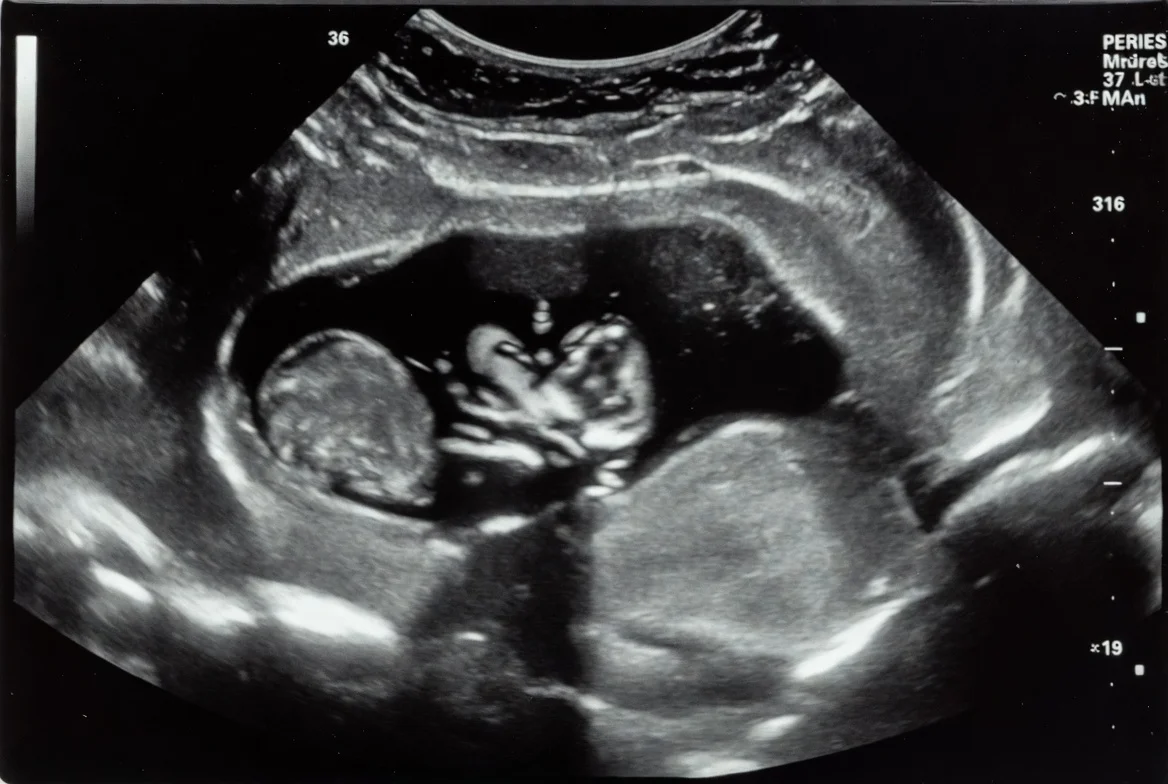

Der Entwurf wollte Abtreibungen bis zur 12. Woche erlauben – bei Vergewaltigung sogar bis zur 16. Woche. Außerdem sollte das Alter für die elterliche Zustimmung von 18 auf 15 Jahre sinken. Albert sagte Nein – und berief sich auf Monacos Identität, die katholische Prägung und den Schutz der Kinder im Mutterleib.

Damit bleibt das Fürstentum eines der wenigen Länder Europas, in dem das Leben ungeborener Kinder nicht der politischen Mode geopfert wird. Abtreibungen bleiben nur in engen Ausnahmefällen möglich: Vergewaltigung, Lebensgefahr für die Mutter oder schwere Fehlbildungen.